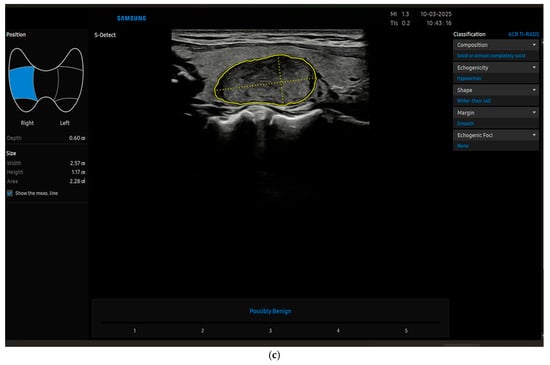

Recently, radiomics is taking its place in thyroid imaging and beyond; it uses extraction algorithms to derive various quantitative features from radiological images, and can be used by machine learning (ML) systems, which is a subset of artificial intelligence (AI) from which deep learning (DL) is derived. These innovative technologies may eventually translate into software used directly by clinicians, namely computer-aided diagnosis (CAD) [10,11] (Figure 1a–c), which is a type of deep learning software.

Figure 1.

(a) The image shows a thyroid nodule characterized by CAD (S-Detect) as benign (later confirmed cytologically and by follow-up) by using K-TIRADS. (b) The image shows the same thyroid nodule characterized by CAD (S-Detect) as benign by using EU-TIRADS (later confirmed cytologically and by follow-up). (c) The image shows the same thyroid nodule characterized by CAD (S-Detect) as benign by using ACR-TIRADS (later confirmed cytologically and by follow-up).